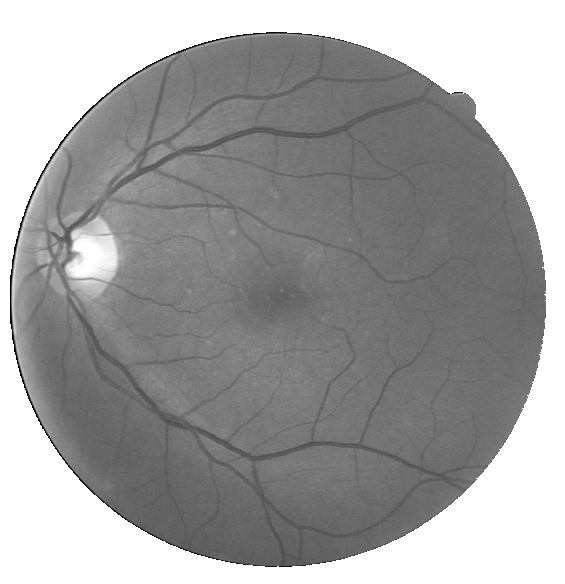

The Sn, Sp, Acc, and AUC values of the best case for the DRIVE database were 0.9119, 0.9742, 0.9667, and 0.9903, while those of the worst case matched 0.7628, 0.9816, 0.9497, and 0.9786, respectively (Fig. 6(a)). For the STARE database, the values of the best case were 0.8527, 0.9936, 0.9837, and 0.9964, while those of the worst case matched 0.7231, 0.9827, 0.9503, and 0.9791 (Fig. 6(b)). Finally, for the CHASE_DB1 database, the values of the best case were 0.8541, 0.9844, 0.9744, and 0.9909, while those of the worst case matched 0.8065, 0.9749, 0.9574, and 0.9808 (Fig. 6(c)).

By jointly evaluating Sn, Sp, and Acc, our method presented the best performance on both the DRIVE and CHASE_DB1 databases. In the DRIVE database, we outperformed all the other works regarding Sn and Acc. In terms of Sp, we stood in sixth; however, knowing that Acc combines information from Sn and Sp, we may conclude that the gain in true detections was much more significant than the inclusion of false detections. In other words, there is a notorious trade-off between Sn and Sp, with our method having a better balance. In the CHASE_DB1 database, we ranked first in all metrics. Regarding the STARE database, we ranked second in all metrics, only behind Neto et al., (2017) in Sn and Liskowski and Krawiec, (2016) in Sp and Acc. By comparing our work with (Neto et al.,, 2017), we see that our Sp is much higher so, given the trade-off abovementioned, the slight disadvantage in terms of Sn sounds natural. In parallel, if we consider the second row of Fig. 6(b), which shows our worst case, we notice that our method failed in rejecting small haemorrhagic blobs, which may have affected Sp. This may be explained by our choice of using 5-fold cross-validation for training, which reduced the number of images with pathological signs, contrary to (Liskowski and Krawiec,, 2016), which used leave-one-out cross-validation.